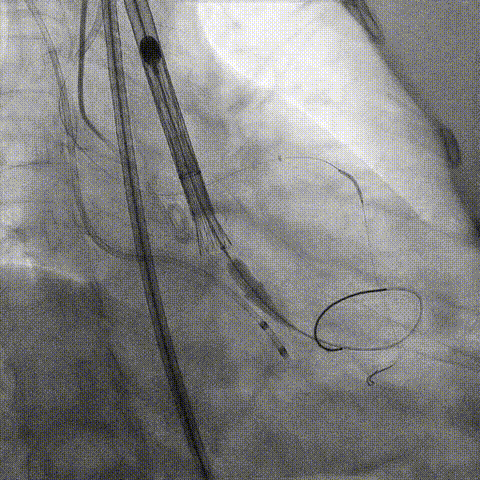

预置Telescope™导引延长导管及导丝保护左冠,

18mm球囊预扩张再次评估冠脉闭塞风险。

Telescope™+Runthrough

18mm*40mm 预扩张

预埋 Resolute Integrity 3.5*26mm

再次评估左冠开口